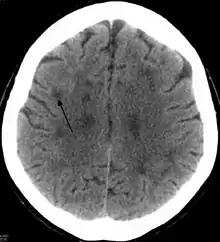

اعتلال بيضاء الدماغ (بالإنجليزية: Leukoencephalopathy) ويسمى أيضاً مرض المادة البيضاءوهو عبارة عن مجموعة من الأمراض المختلفة التي تؤثر على المادة البيضاء للدماغ، والتي تضمن موت الخلايا في مناطق محددة منها، مثل التهاب بيضاء الدِّماغ، أو حثل المادة البَيضاء.[1][2][3] يعد هذا المرض أو هذه الأعراض هو تغييرات هيكلية في الدماغ في الخلايا العصبي المركزي، وتلف المايلين كما السمة الرئيسية، تلعب آفات الدماغ المتقدمة التي تنطوي على وظائف متخصصة للمساحات المادة البيضاء. المظاهر السريرية من التغييرات الغفلة والنسيان وشخصيته، إلى الخرف، والغيبوبة وحتى أحياناً الوفاة.